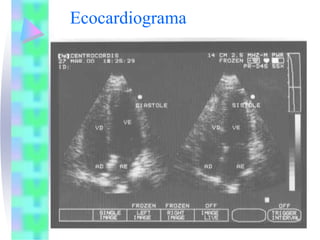

Ecocardiograma

-   Tamanho e função das câmaras

-   Válvulas

-   Espessura das paredes e septo

-   Movimento das paredes

-   Aorta

-   Pericárdio

-   Artéria pulmonar

-   Trajeto de saída ventricular direito

-   Lesões comunicantes

• Doppler:

- Utiliza a direção e a velocidade do fluxo sanguíneo

para avaliar a hemodinâmica cardiovascular

- Imagem com fluxo em cores: fornece a visualização

bidimensional do fluxo sanguíneo

• Ecocardiograma de contraste:

- Veias cavas

- Cardiopatias congênitas complexas

Ecocardiograma - Tamanho e função das câmaras - Válvulas - Espessura das paredes e septo - Movimento das paredes - Aorta - Pericárdio - Artéria pulmonar - Trajeto de saída ventricular direito - Lesões comunicantes

Ecocardiograma • Doppler: - Utilizaa direção e a velocidade do fluxo sanguíneo para avaliar a hemodinâmica cardiovascular - Imagem com fluxo em cores: fornece a visualização bidimensional do fluxo sanguíneo • Ecocardiograma de contraste: - Veias cavas - Cardiopatias congênitas complexas